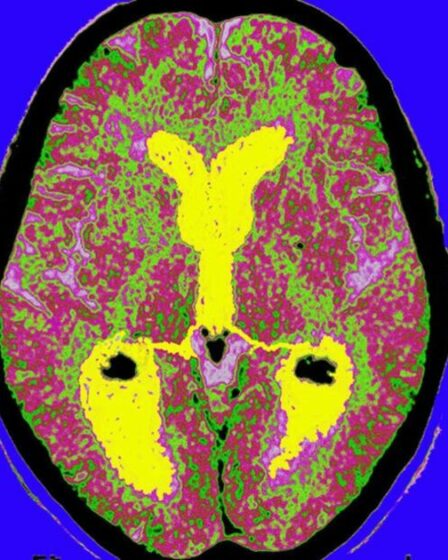

Des cerveaux préservés vieux de 12 000 ans pourraient apporter des réponses sur la maladie d’Alzheimer

Une archive remplie de vieux cerveaux humains pourrait aider les scientifiques à mieux comprendre comment les tissus mous sont préservés – et faciliter la recherche sur les maladies neurodégénératives. Le cerveau est constitué d’environ trois …

Selon une étude sur la maladie d’Alzheimer transmise par des cadavres

La maladie d’Alzheimer peut être transmise aux humains traités à l’aide d’hormones extraites de cadavres, ont découvert des scientifiques. Des chercheurs ont découvert que cinq personnes traitées avec de l’hormone de croissance humaine (HGH) extraite …